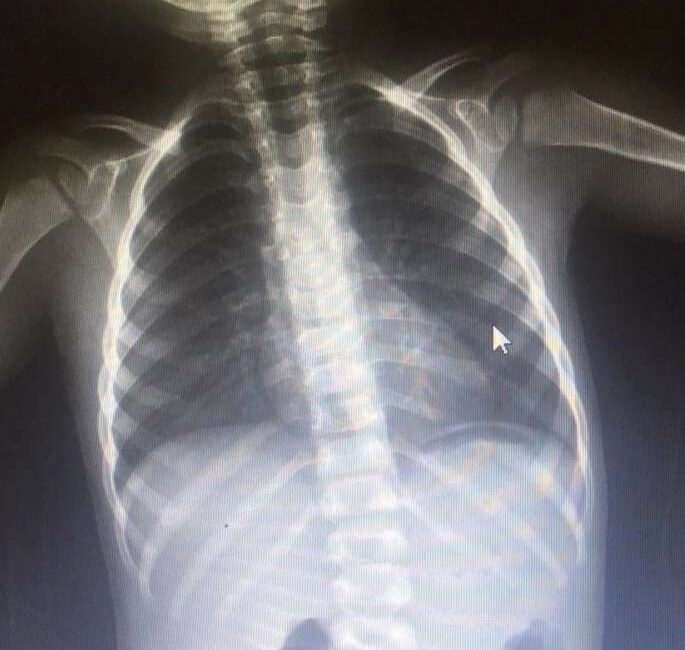

A.K. (2), evde oynarken yerde bulduğu çiviyi ağzına atıp yuttu.

Olayı gören ailesi, küçük çocuğu hemen özel araçla İnegöl Devlet Hastanesi’ne götürdü.

Yapılan tetkiklerde çivinin midesinde olduğu tespit edilen çocuk, ambulansla Bursa Yüksek İhtisas Eğitim ve Araştırma Hastanesi’ne sevk edildi.